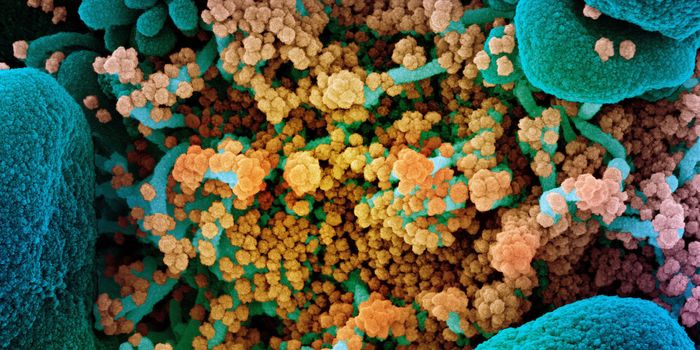

APR 20, 2020Cell & Molecular BiologyThe SARS-CoV-2 virus causea huge range of symptoms, and researchers are learning more about the worst cases, which may h ...

SEP 01, 2021MicrobiologyIt's been generally assumed that people who get infected with SARS-COV-2 will develop antibodies to the virus, which cau ...